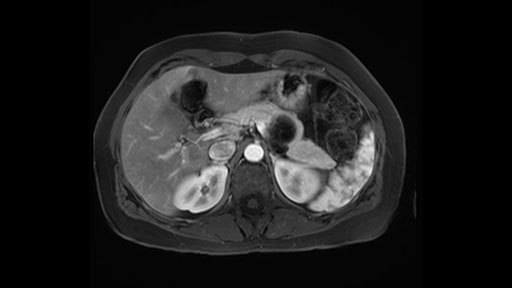

The slowing down moments or considerations that I give when I look at the scan and plan my distal pancreatectomy is how far away the tumor is to the portal vein and do I have to formally create a tunnel behind the pancreas on top of the portal vein or do I have to take the pancreas further to the left of the portal vein or the patient’s left of the portal vein. So here I can see that here is the tumor here. I can see that the tumor is a fair way away to the patient’s right and so I will likely not have to take or create the tunnel formally in this procedure. And that speaks a lot to the resection margins. So its important when you’re doing a distal pancreatectomy or any procedure potentially for oncologic reasons to get clearance of the tumor and to take the tumor kind of intact.

Key features that I look at the imaging are: first I look at the distance between the cyst and the portal vein SMV confluence. So there are guidelines for this, they call the Yonsei guidelines, to decide to do it laparoscopically or open and basically it says that if it’s a cancer, at least a centimeter away from the celiac trunk or the venous confluence. This is a cyst. So maybe you could stretch that a bit, but you don't want to get into trouble there. So for this cyst if you look at it, it's nicely away from the confluence.

So unfortunately I cannot show you a coronal view but you can see it easily on this scan, going down first you see the celiac trunk and you see here, quite a nice distance between the celiac trunk and the beginning of the mucinous cyst. And if you go up here and follow down the portal vein confluence you also see a nice distance there.